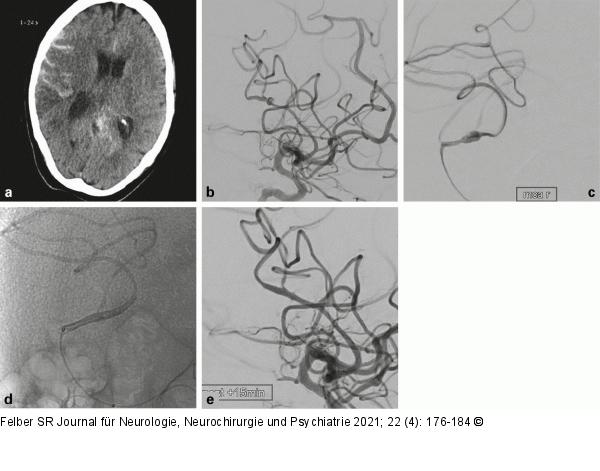

Abbildung 5a-e: Mykotisches Aneurysma 51-jähriger Patient mit infizierter künstlicher Herzklappe und plötzlich aufgetretenen Kopfschmerzen und Hemiparese links. Die CT ergab eine akute Subarachnoidalblutung und Ischämie im Mediaterritorium rechts (a). Die DSA wies ein „mykotisches“ fusiformes Aneurysma des hinteren parietalen Mediahauptastes als Blutungsquelle nach (b). Die lokale Darstellung über den Mikrokatheter zeigte den Mediaast vor (c) und nach (d) der Implantation eines Flow Diverters (p48-HPC, Phenox, Bochum, Deutschland). Im Abschlußbild (e) war das Aneurysma aus der Zirkulation ausgeschaltet. Nach der Freisetzung des Flow Diverters wurde die gewichtsadaptierte Loading Dose Eptifibatid (Integrilin®, Glaxo Smith Kline, München, Deutschland) intraarteriell und Erhaltungsdosis intravenös über 24h gegeben, danach erhielt der Patient Ticagrelor 2 × 90 mg/d als Monotherapie. |

Abbildung 5a-e: Mykotisches Aneurysma